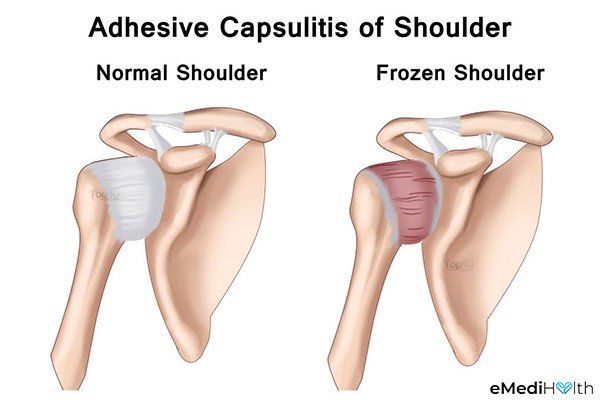

What is Frozen Shoulder?

Frozen shoulder, medically known as adhesive capsulitis, is a condition characterized by the gradual and often painful loss of motion in the shoulder joint. It typically progresses through stages, each marked by varying degrees of pain and stiffness. The hallmark feature of frozen shoulder is the thickening and tightening of the joint capsule—the connective tissue that surrounds the shoulder joint. This tightening restricts the joint’s ability to move freely.

Image taken from https://www.emedihealth.com/ wellness/fitness/ relieve-frozen-shoulder